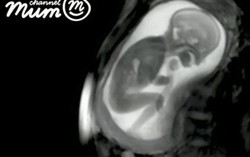

Phòng & chữa bệnh 15:48 10/02/2017Với công nghệ chụp cộng hưởng từ tân tiến nhất, hình ảnh của em bé mới 20 tuần tuổi đạp, cười thậm chí là nhảy múa trong bụng mẹ rõ mồn một đã khiến cả thế giới kinh ngạc.